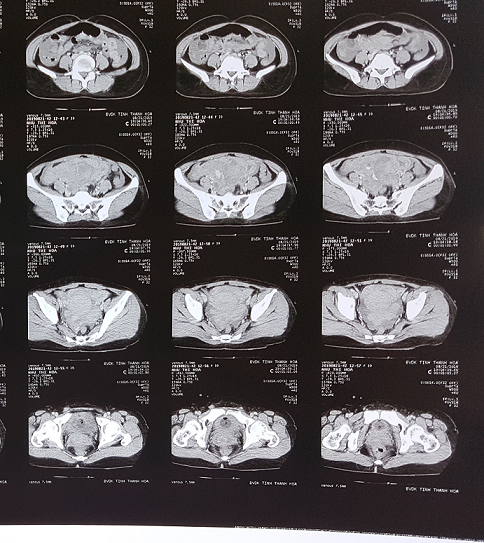

CLS: Siêu âm: dịch màng phổi phải 60mm, dịch ổ bụng 20mm, tổn thương khối hỗn hợp âm hạ vị. XQ lồng ngực: mờ toàn bộ phổi phải . CTM: HC 2,04T/L, HST 60g/l, Hematocrite 17,7%, TC: 100G/L. Test que thử thai 3 lần đều 2 vạch, βHCG 3334 m IU/ml

Kết quả chụp CT lồng ngực không thấy u cục gì, chụp CT ổ bụng có nhiều dịch máu trong ổ bụng, khối tổn thương ổ bụng vùng hạ vị lệch phải nghi ngờ là chửa ngoài tử cung, có hình ảnh thoát thuốc.